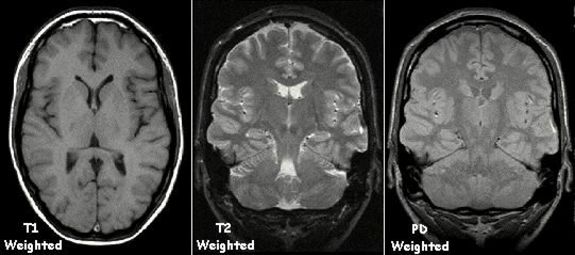

Inverse Probleme sind ein Gebiet der Angewandten Mathematik, in dem Rückschlüsse gezogen werden: entweder soll aus indirekten Beobachtungen auf deren Ursachen geschlossen werden. Oder man möchte die Ursachen eben genau so einstellen, dass gewünschte Effekte eintreten. Was das konkret bedeutet, wird zunächst anhand des klassischen Problems der Computertomographie beleuchtet. Ultraschalltomographie und Magnetresonanztomographie sind weitere Beispiele aus dem aktuellen Forschungsbereich der Vortragenden. Einen kleinen Einblick in die mathematischen Besonderheiten inverser Probleme liefern dann elementare Problemstellungen zum "Mitrechnen".

MRI Scan des Gehirns

© KieranMaher_wikipedia